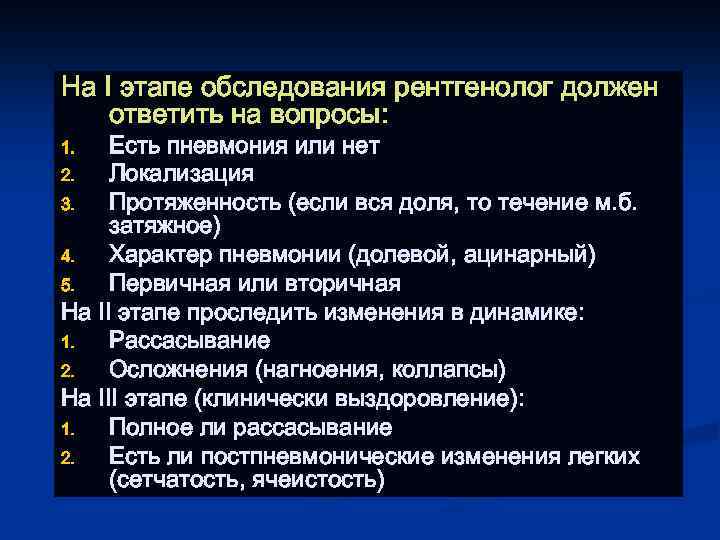

На I этапе обследования рентгенолог должен ответить на вопросы: Есть пневмония или нет 2. Локализация 3. Протяженность (если вся доля, то течение м. б. затяжное) 4. Характер пневмонии (долевой, ацинарный) 5. Первичная или вторичная На II этапе проследить изменения в динамике: 1. Рассасывание 2. Осложнения (нагноения, коллапсы) На III этапе (клинически выздоровление): 1. Полное ли рассасывание 2. Есть ли постпневмонические изменения легких (сетчатость, ячеистость) 1.